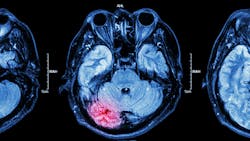

When a patient arrives in your office after mouth or jaw trauma, how can you tell if they had a concussion or traumatic brain injury (TBI)?

You can ask questions, run tests, and take traditional x-rays, but these methods do not provide the data necessary to see what's really going on. These types of scans only provide a snapshot of the spine in a fixed position, so you receive a static image at one point in time. Therefore, it is impossible to see the full scope of what is happening with the spine and brain.

Real-time motion-guided imaging with qEEG and brain-spine communication metrics provide medical evidence of both brain and spinal dysfunction so you can provide a better diagnosis and treatment.

Digital video images are taken to detect vertebral alignment in motion while stabilizing individual vertebral levels rather than offering a single image. This non-invasive assessment of both the brain and the spine provide quantitative, objective, and visual data (down to the tenth of a millimeter) that is consistent, reliable, and accessible via a HIPAA compliant cloud-based system.

When patients also receive a brain baseline assessment, it's possible to track improvements or changes (especially after injuries) of brain performance and spinal motion. An FDA-cleared qEEG with an ERP can be used to take a map of the brain and obtain a benchmark of "normal" brain activity.